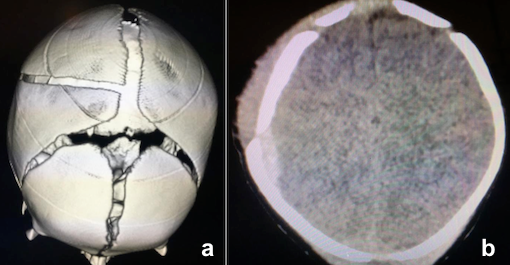

A questo punto veniva eseguita una TC cranio, che rivelava la presenza di una frattura parietale destra a decorso arcuato, lievemente scomposta e un ematoma subdurale parietale destro dello spessore massimo di 7 mm e un consensuale ematoma dei tessuti molli extracranici sub-galeali in regione fronto-temporale destra (Figura 1). Sulla base del quadro neuroradiologico, la consulenza neurochirurgica poneva indicazione al prosieguo dell’osservazione clinica in ambiente ospedaliero per ulteriori 48 ore con rivalutazione neuroradiologica a distanza.

In presenza di benessere clinico, dopo 48 ore, si procedeva alla dimissione della neonata. A distanza di una settimana un controllo TC (RM encefalo non disponibile) evidenziava la riduzione dell’ematoma epidurale parietale destro (spessore massimo 5 mm). Successivo follow-up clinico nella norma.